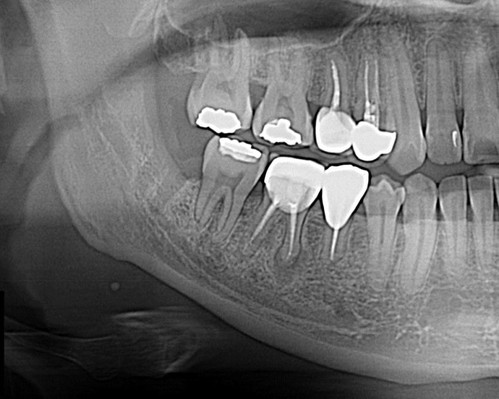

이 환자의 경우 다른 환자와 다른 것

이 사랑니가 누워있지 않고 서있어서 오히려 교정력을 주기가 더 어려웠다.